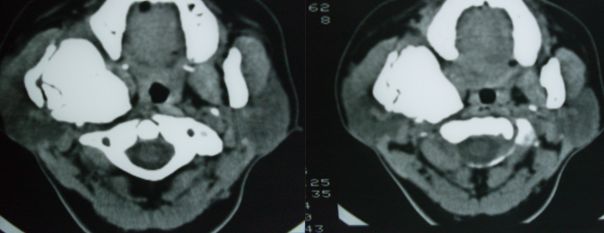

标题: CT12916:求助 F/44 右聂部肿痛一年余 [打印本页]

标题: CT12916:求助 F/44 右聂部肿痛一年余

是什么肿瘤

右侧下颌骨升支单骨病变,考虑非骨化纤维瘤可能。图片模糊,期等结果。